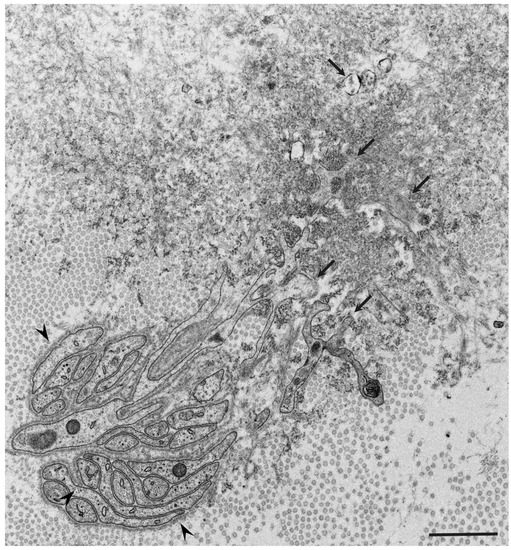

- Koike, H.; Ikeda, S.; Takahashi, M.; Kawagashira, Y.; Iijima, M.; Misumi, Y.; Ando, Y.; Ikeda, S.-I.; Katsuno, M.; Sobue, G. Schwann cell and endothelial cell damage in transthyretin familial amyloid polyneuropathy. Neurology 2016, 87, 2220–2229. [Google Scholar] [CrossRef]

- Koike, H.; Nishi, R.; Ikeda, S.; Kawagashira, Y.; Iijima, M.; Sakurai, T.; Shimohata, T.; Katsuno, M.; Sobue, G. The morphology of amyloid fibrils and their impact on tissue damage in hereditary transthyretin amyloidosis: An ultrastructural study. J. Neurol. Sci. 2018, 394, 99–106. [Google Scholar] [CrossRef] [PubMed]

- Koike, H.; Mouri, N.; Fukami, Y.; Iijima, M.; Matsuo, K.; Yagi, N.; Saito, A.; Nakamura, H.; Takahashi, K.; Nakae, Y.; et al. Two distinct mechanisms of neuropathy in immunoglobulin light chain (AL) amyloidosis. J. Neurol. Sci. 2021, 421, 117305. [Google Scholar] [CrossRef] [PubMed]